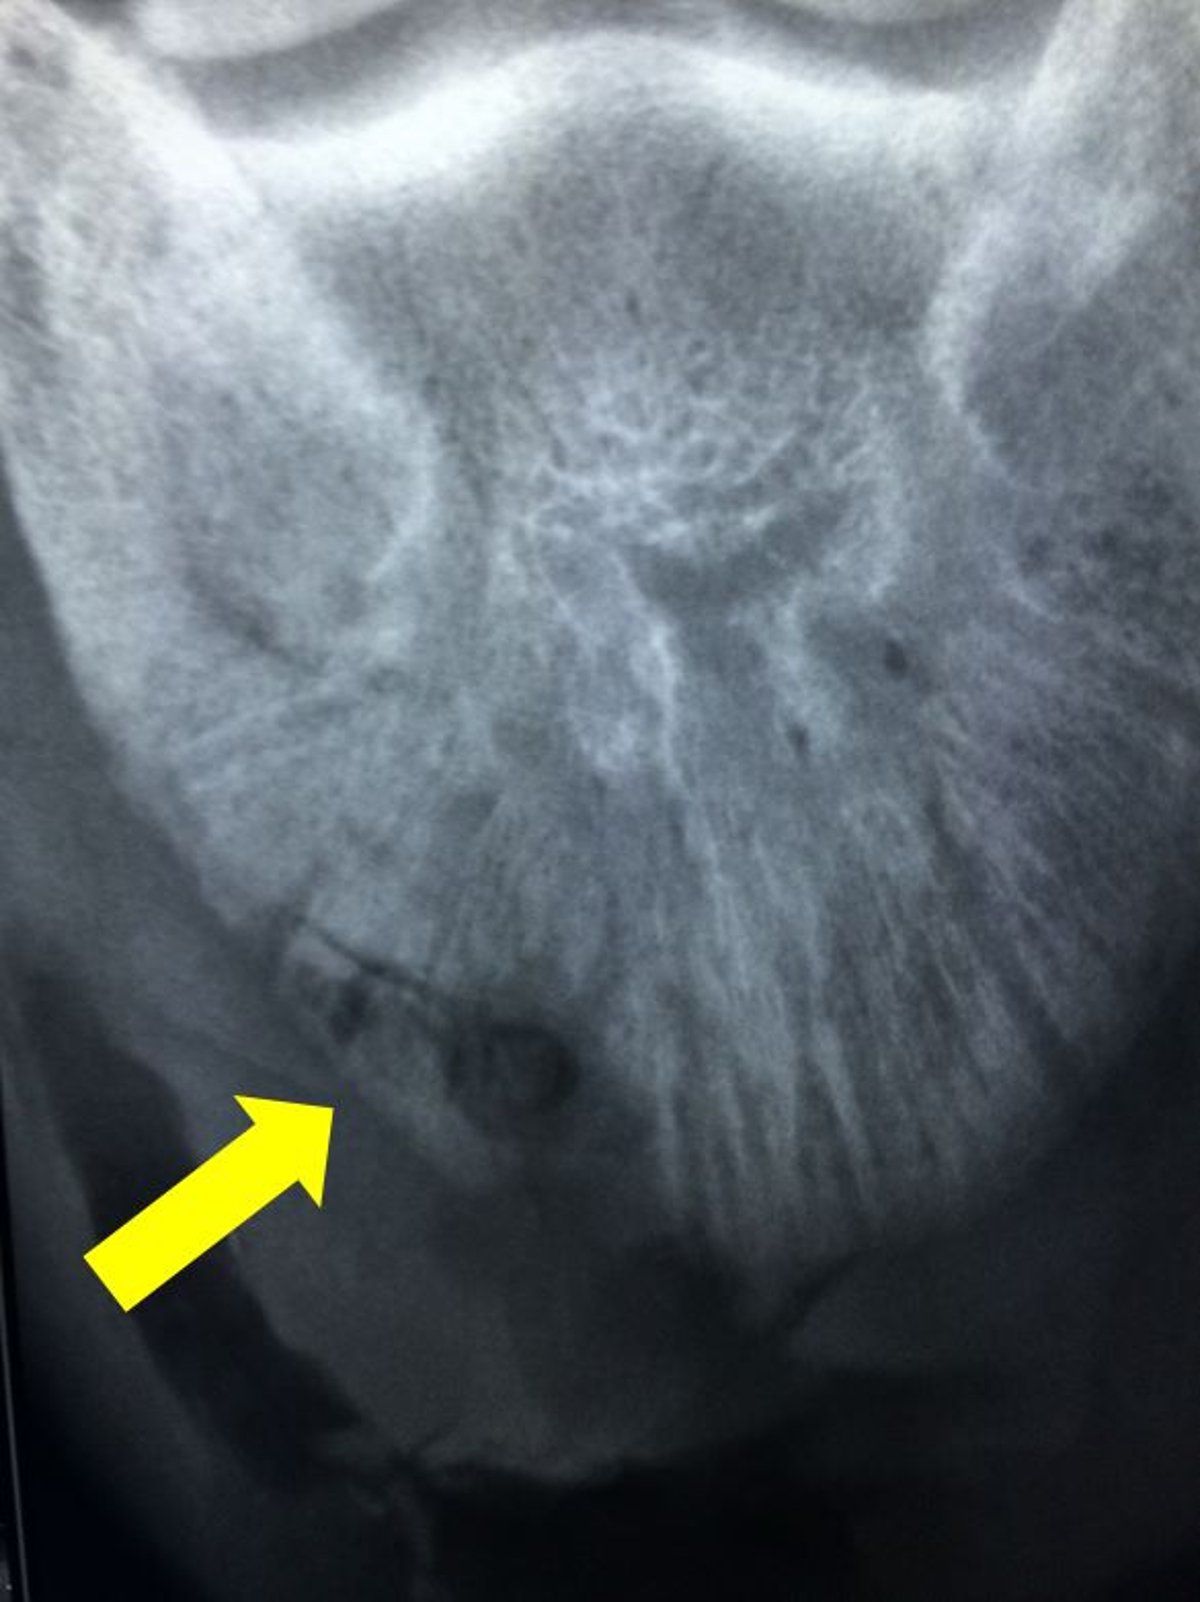

Imagen radiográfica que muestra un sequestrum (flecha) en la cara dorsolateral de la falange distal en un caballo. Obsérvese la zona circular en la que se ha desbridado la suela a lo largo del aspecto axial del secuestro.

Cortesía de la Dra. Valerie J. Moorman.